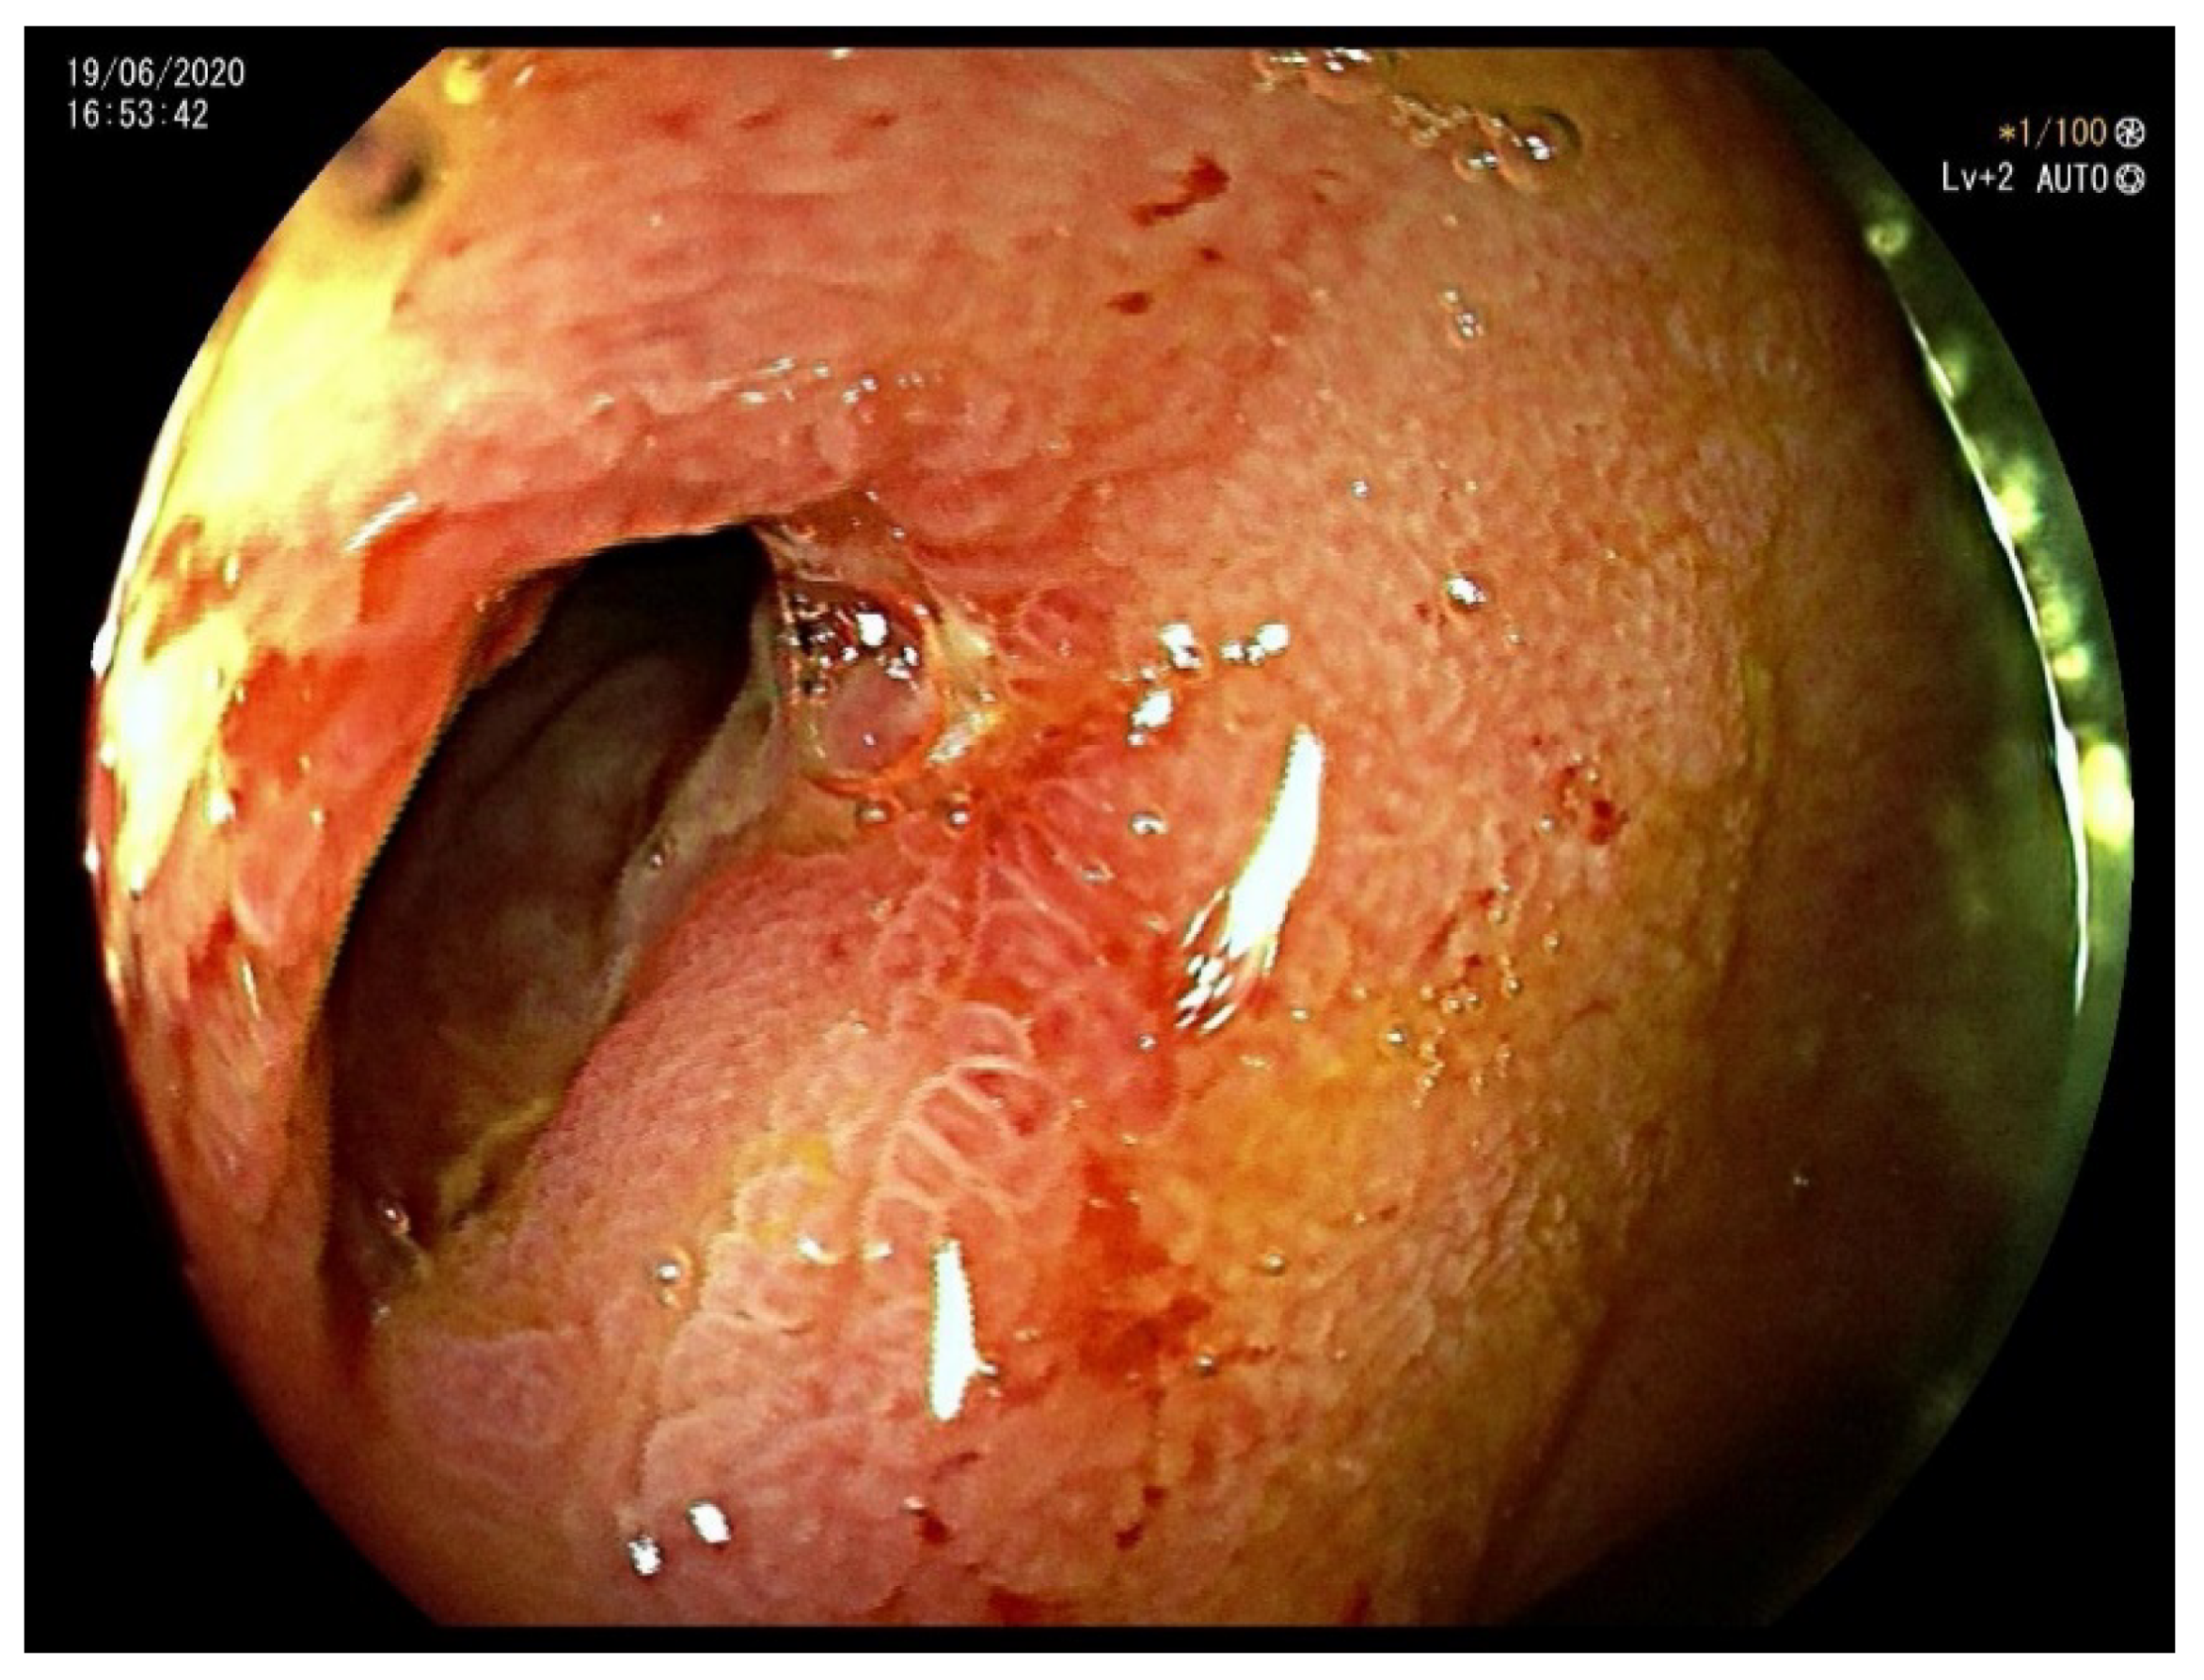

1.1. Case 1